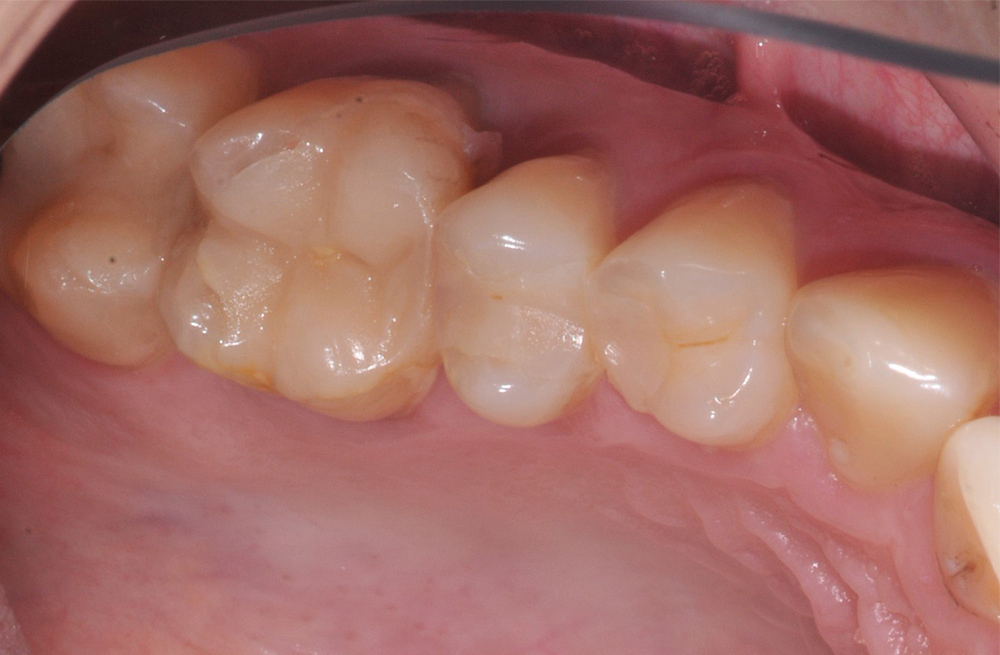

Восстановление жевательной группы зубов швейцарским имплантатом и цельнокерамической реставрацией